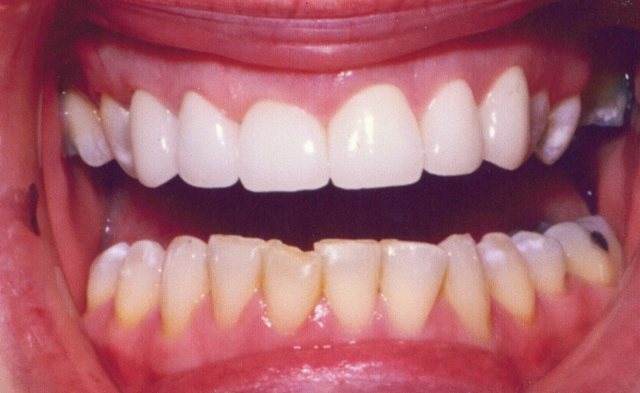

Περιστατικό 1 | Περιστατικό 2 | Περιστατικό 3 |

Περιστατικό 1 | Περιστατικό 2 |

Περιστατικό 3 | Περιστατικό 4 | Περιστατικό 5 |

Περιστατικό 1 | Περιστατικό 2 | Περιστατικό 3 |

Περιστατικό 1 | Περιστατικό 2 |

Περιστατικό 3 | Περιστατικό 4 | Περιστατικό 5 |

Περιστατικό 1 | Περιστατικό 2 |